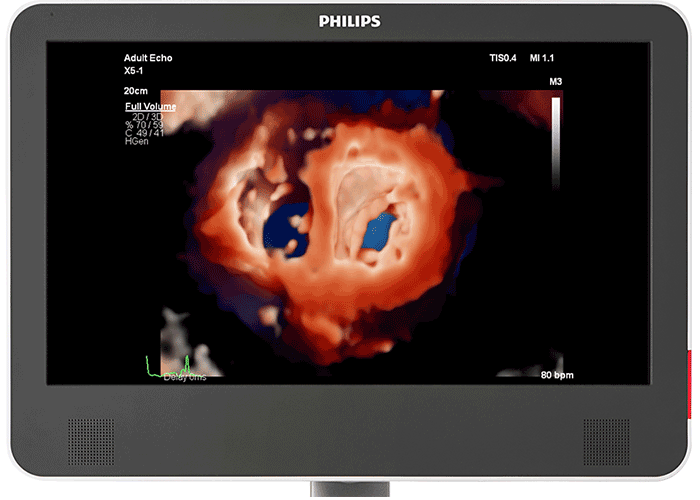

仮想光源によるフォトリアリスティックな3D画像 心臓組織用 TrueVue と仮想光源により、欠損部位や構造の奥行きの把握が容易になり、経胸腔の心臓組織および経食道エコーの視覚化も向上します。新型 EPIQ CVx Transcend を見た臨床医の 90%⁵が、新しい TrueVue 3D フォトリアリスティックレンダリングにより組織構造がより理解しやすく表示されるため、臨床的確信を強く持つことができると回答しました。

インターベンションとのコラボレーション用に開発されたフォトリアリスティックレンダリング 循環器用 TrueVue は、仮想光源を使用してデバイスの視認性を向上させる、新しい 3D 超音波表示方法です。TrueVue は、組織の詳細と奥行き方向の情報を分かりやすく示す画像を提供して、カテーテルおよびデバイスの位置の把握を容易にします。エコー画像がより分かりやすく表示されることで、インターベンション医は確信を持って処置を行うことができます。新型 EPIQ CVx Transcend を見た臨床医の 90%⁵が、新しい TrueVue 3D フォトリアリスティックレンダリングにより組織構造の表示が改善されるため、臨床的確信を強く持つことができると回答しました²。